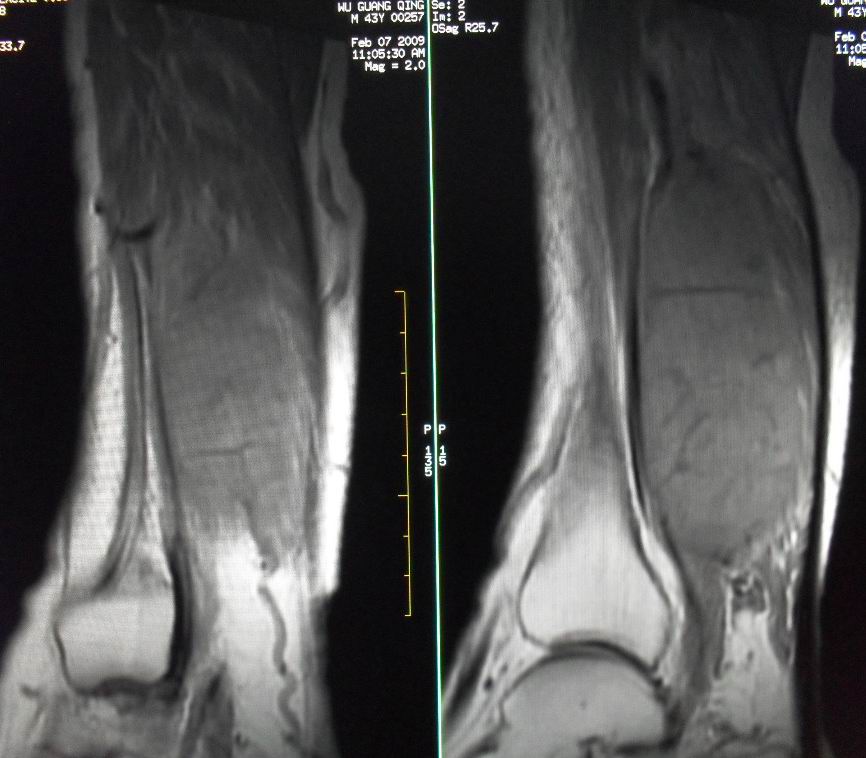

患者男43,右小腿后部软组织肿块2~3年,近期增大明显。平扫加强化。已手术。

1)呈等长t1混杂t2信号,其内见多发类圆形长t1长t2异常信号,病灶主要沿肌间隙生长,但有完整的包膜.gd_dtpa显示:病灶呈明显不均匀的强化,但未见迂曲的强化血管影.

呈等长t1混杂t2信号,其内见多发类圆形长t1长t2异常信号,病灶主要沿肌间隙生长,但有完整的包膜